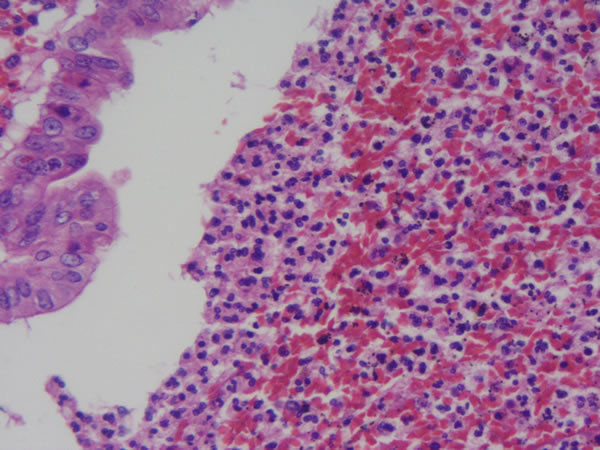

Intestino grosso - epitélio cilíndrico simples + epitélio secretor (células caliciformes) Neoplasia -adenocarcinoma de cólon Lado esquerdo: intestino normal Lado direito: Neoplasia |

Intestino grosso - Neoplasia - adenocarcinoma de cólon Note que as células neoplásicas não têm produção de muco. Epitélio pseudo-estratificadoe há aumento da relação núcleo/citoplasma e da densidade da cromatina |

Intestino grosso Neoplasia - adenocarcinoma de cólon Células neoplásicas invadiram a camada muscular lisa |

Intestino grosso Neoplasia -adenocarcinoma de colon Células neoplásicas invadindo submucosa Notar as células normais no canto superioe esquerdo |

| A | Intestino grosso Neoplasia - adenocarcinoma de colon bem diferenciado Outros achados: necrose, infl. aguda e crônica Lado D normal Lado E neoplásicas |